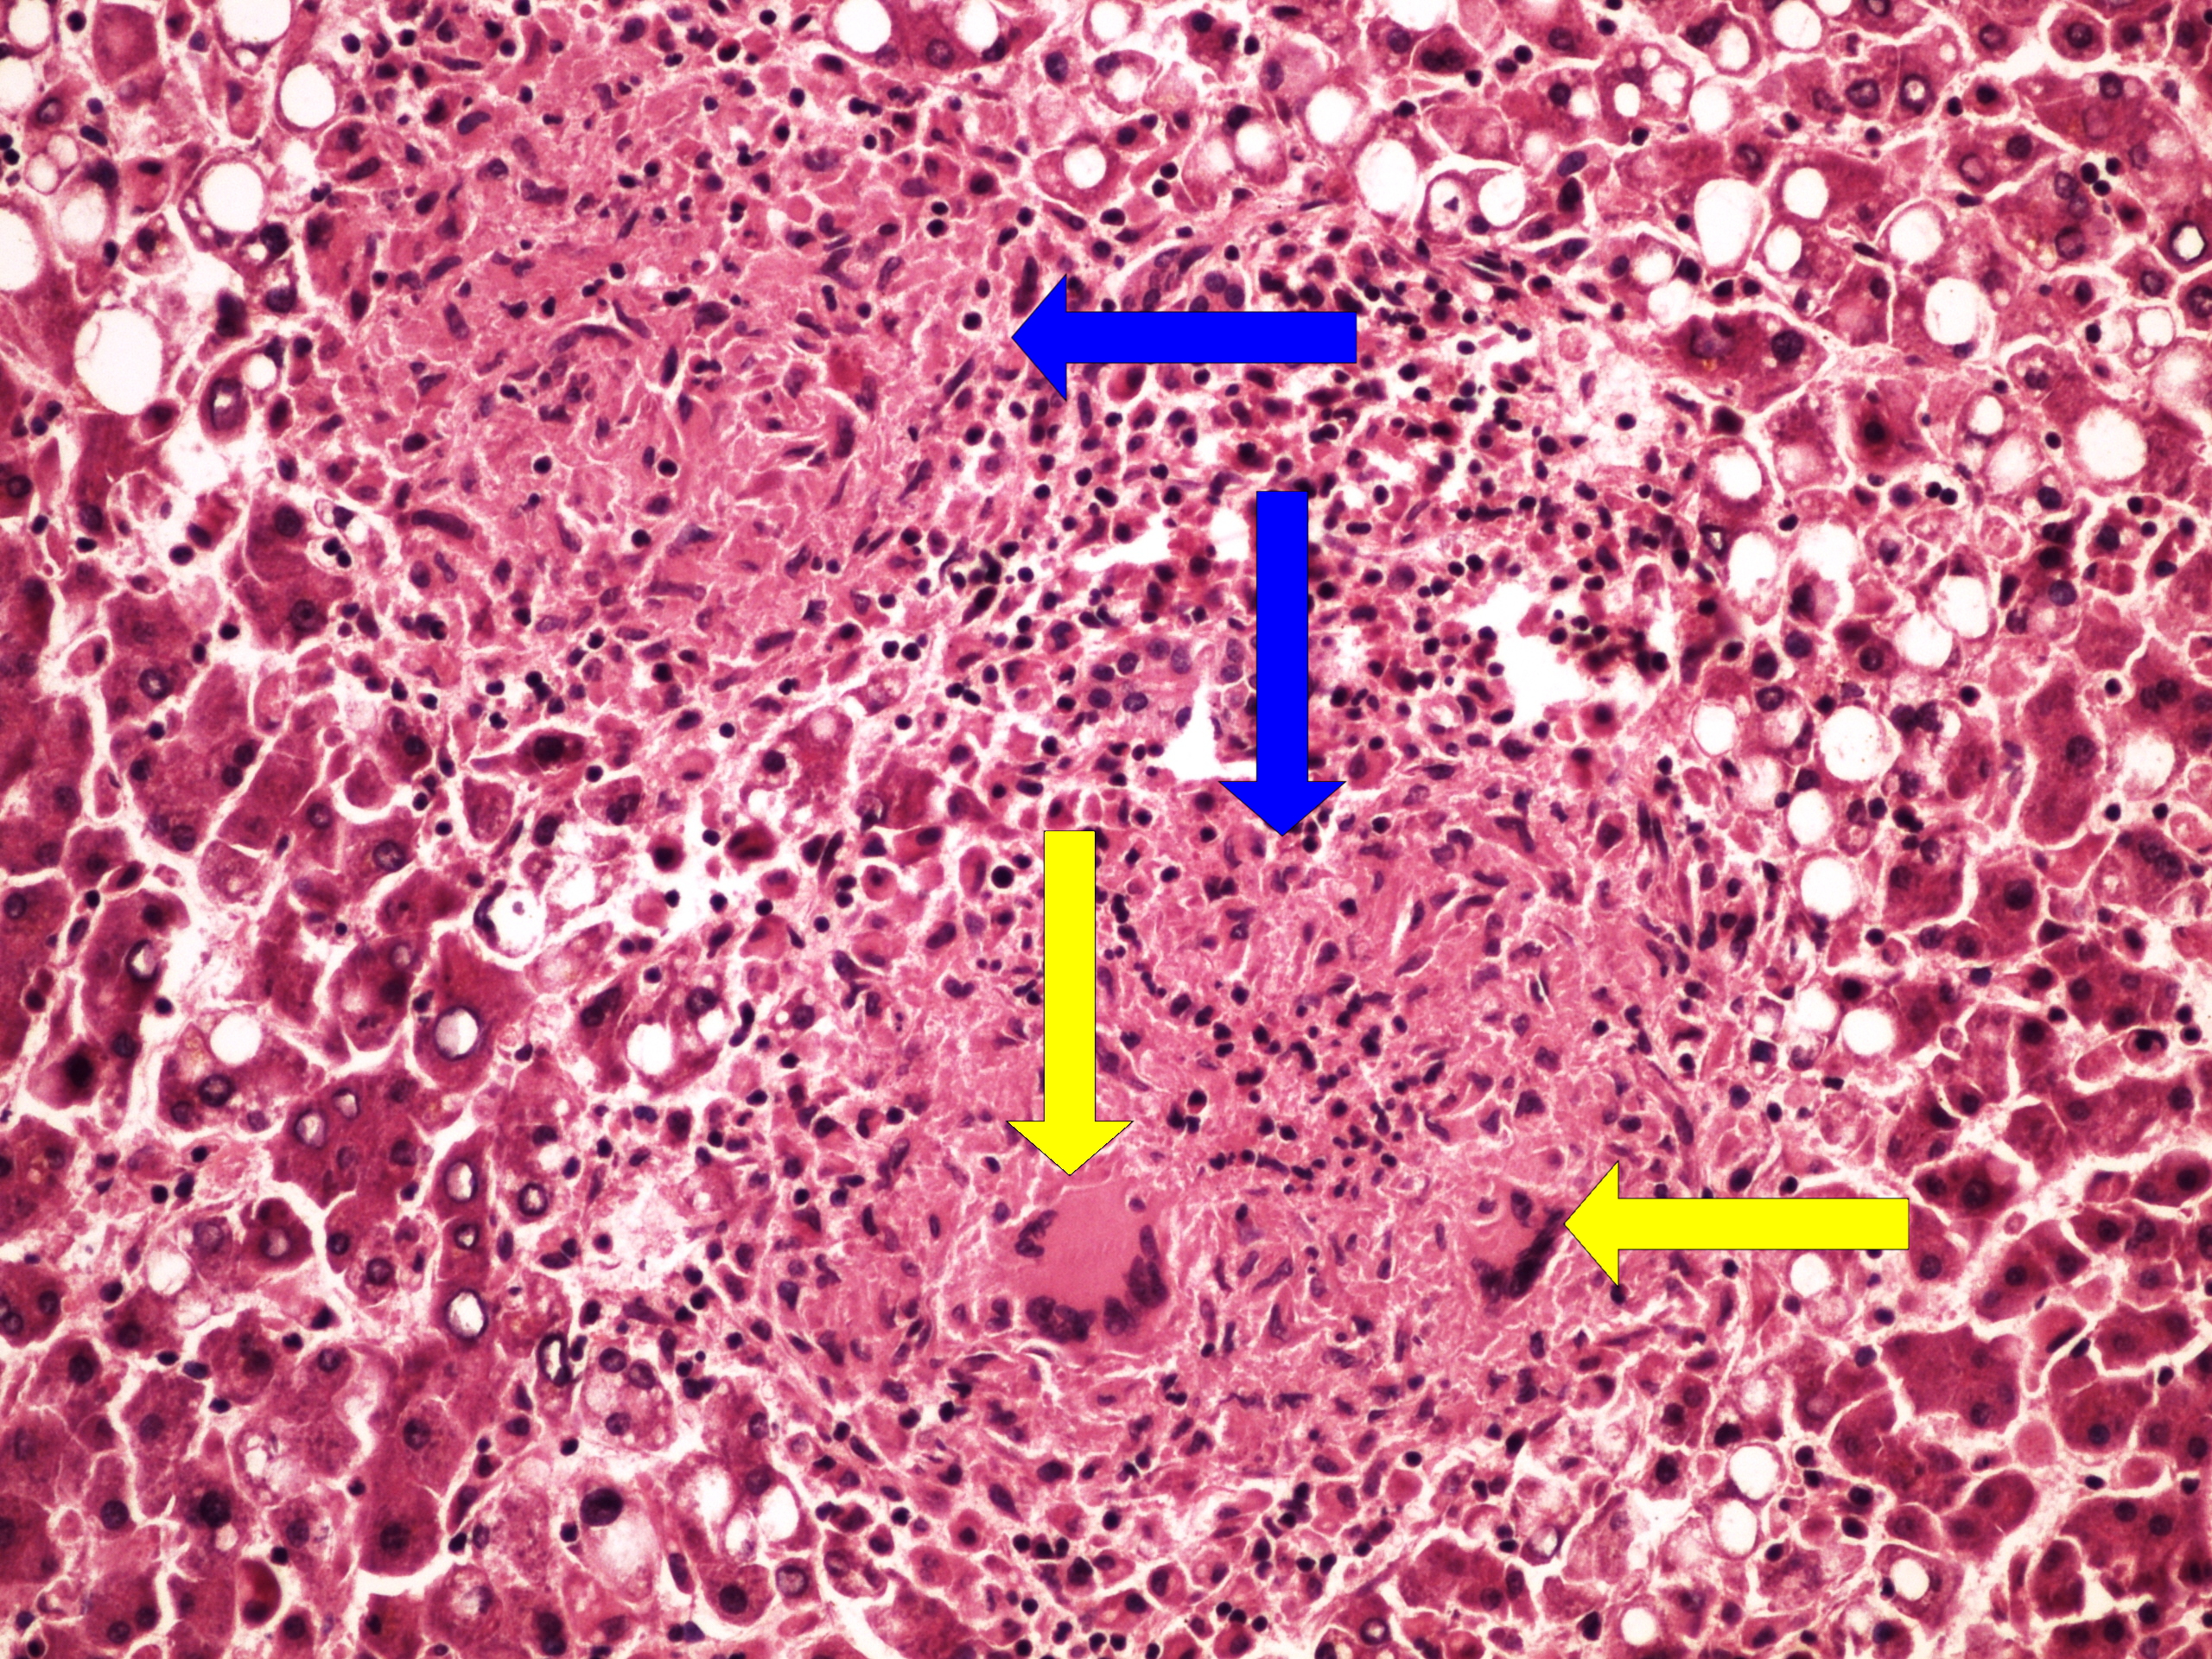

Preparát č.25 a č.26 - miliární TBC jater

Struktury

- miliární uzlík

- vícejaderné buňky Langhansova typu